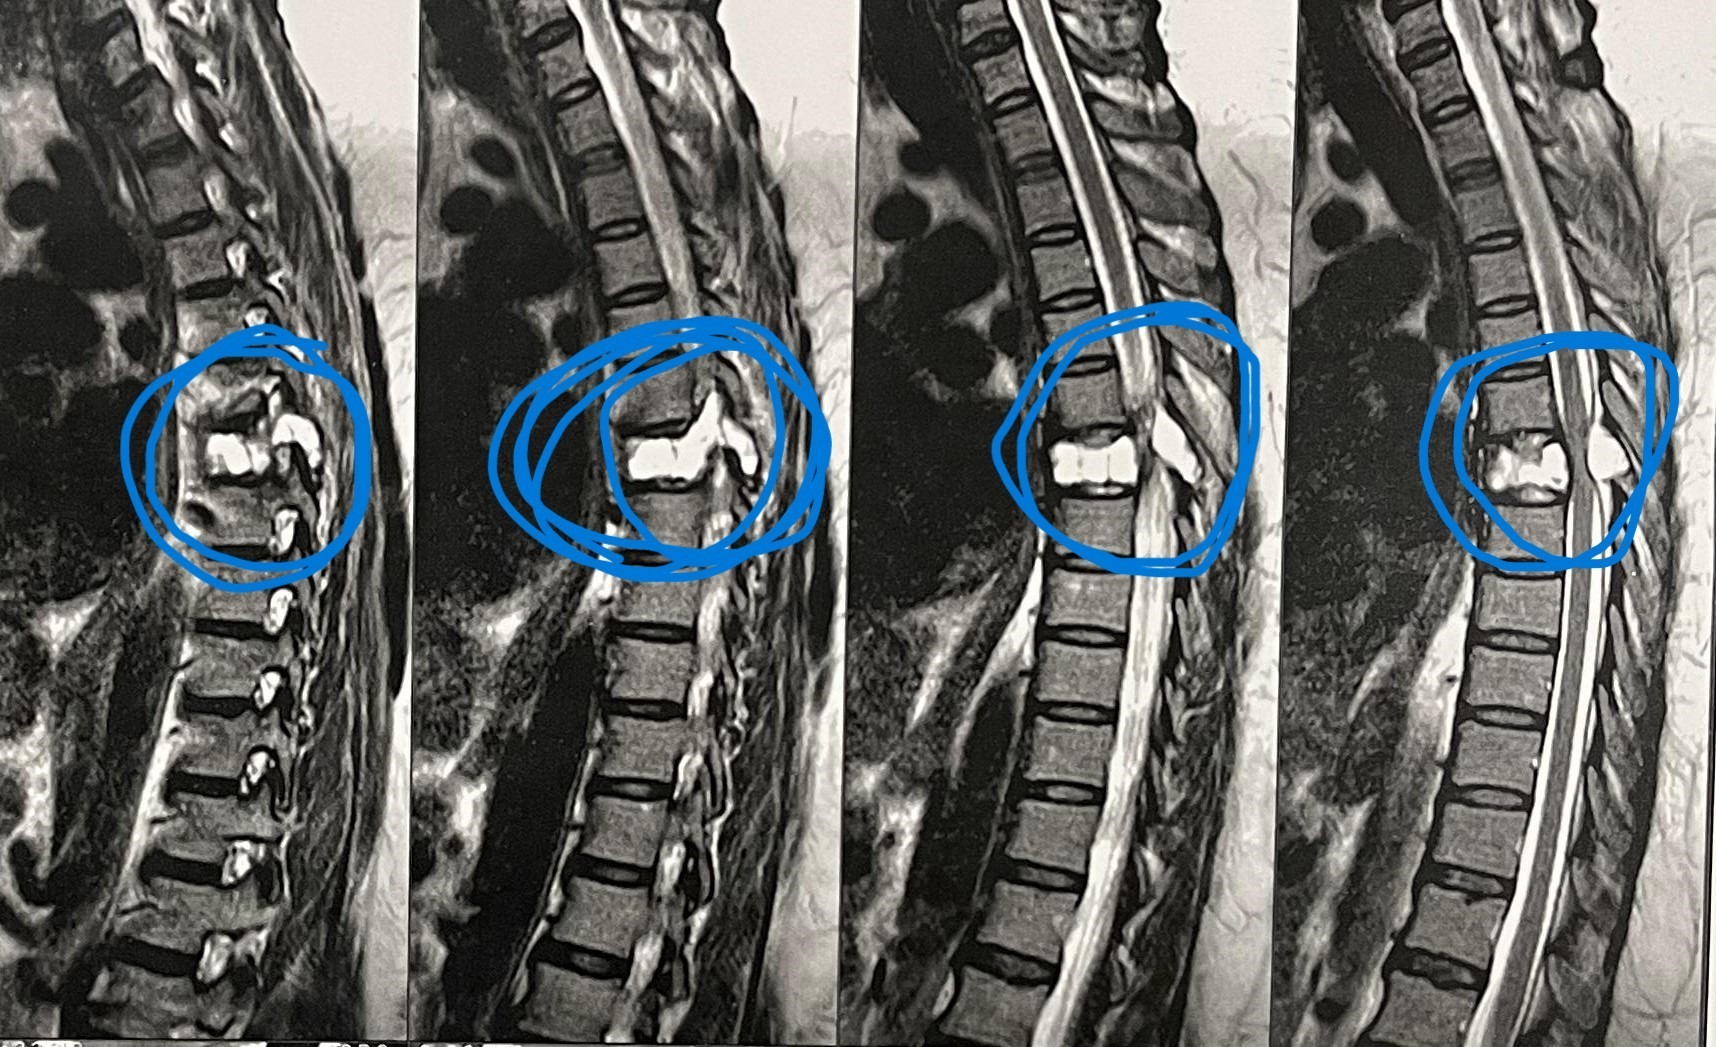

مريضة عمرها 43 عام تعاني من ضعف متزايد بالطرفين السفليين.

43-year-old female patient suffers from increasing weakness in the lower extremities

A 43-year-old woman suffering from progressive weakness in both lower limbs was diagnosed and treated. This condition affects walking ability and mobility, requiring thorough neurological evaluation to determine the underlying cause and develop an appropriate treatment plan.